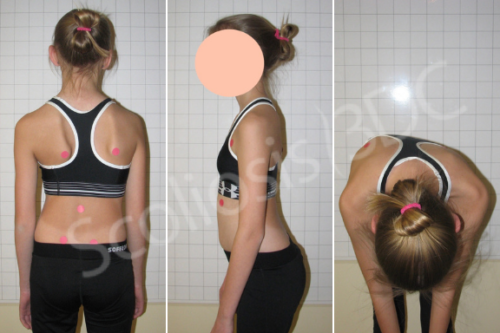

سابعًا: ما هو Rib Hump (بروز الضلوع)؟

في بعض الحالات، قد يلاحظ الأهل بروزًا في أحد جانبي الظهر عند الانحناء للأمام.

📌 هذا يسمى Rib Hump، ويحدث بسبب دوران الفقرات وليس فقط بسبب الانحناء الجانبي.

👉 لذلك، فهو علامة مهمة على وجود اعوجاج ثلاثي الأبعاد وليس مجرد مشكلة شكلية.

👉 وبالتالي، قد يلاحظ الأهل علامات مثل:

- عدم تساوي الكتفين

- ميلان في الجسم

- اختلاف مستوى الحوض